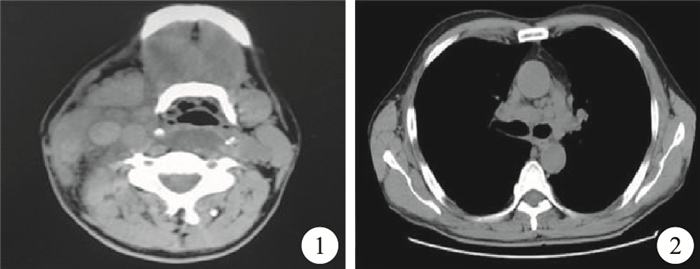

臨床資料 患者,男,48歲。以肺大泡、頸部、縱隔淋巴結腫大收入院。患者入院前4 d無明顯誘因出現右頸部及鎖骨上區腫脹,伴高熱(體溫最高38.8 ℃),有明顯壓痛,頸部活動受限。頸部CT示:右頸部血管間隙內、兩側鎖骨上窩多發性異常密度灶;右側頸靜脈增粗(圖 1)。胸部X線片示:不除外右上肺肺大泡、右上肺結節。胸部CT示:肺氣腫、肺大泡;右肺上葉斑片狀高密度影;縱隔內有多發增大的淋巴結(圖 2)。患者入院后持續低熱,但多次查血常規及生化檢查未見明顯異常,更換多種抗生素均未能控制發熱,后行右側頸部淋巴結穿刺,病理報告示腺癌,消化道轉移的可能性大。進一步復查消化道腫瘤標記物、腹部CT、胃鏡及鋇灌腸,均未見明顯異常。再次行左側頸部淋巴結穿刺,并行免疫組織化學及專科醫院會診為印戒細胞癌,免疫組織化學檢查結果不支持消化道來源,肺腺癌標記物甲狀腺轉錄因子-1 (TTF-1)陰性。結合患者影像學檢查,臨床診斷為肺原發性印戒細胞癌,縱隔、鎖骨上區及頸部多發性淋巴結轉移。明確診斷后,給予4個周期化療,方案為培美曲塞二鈉+順鉑,化療結束后,復查胸腹部CT等檢查,癌瘤進展,肺內原發結節增長并出現肺內轉移結節及腦轉移結節,患者因肺部炎癥、持續發熱再次入院,給予抗炎、抗腫瘤及增強免疫力等治療,2個月后因呼吸衰竭死亡。